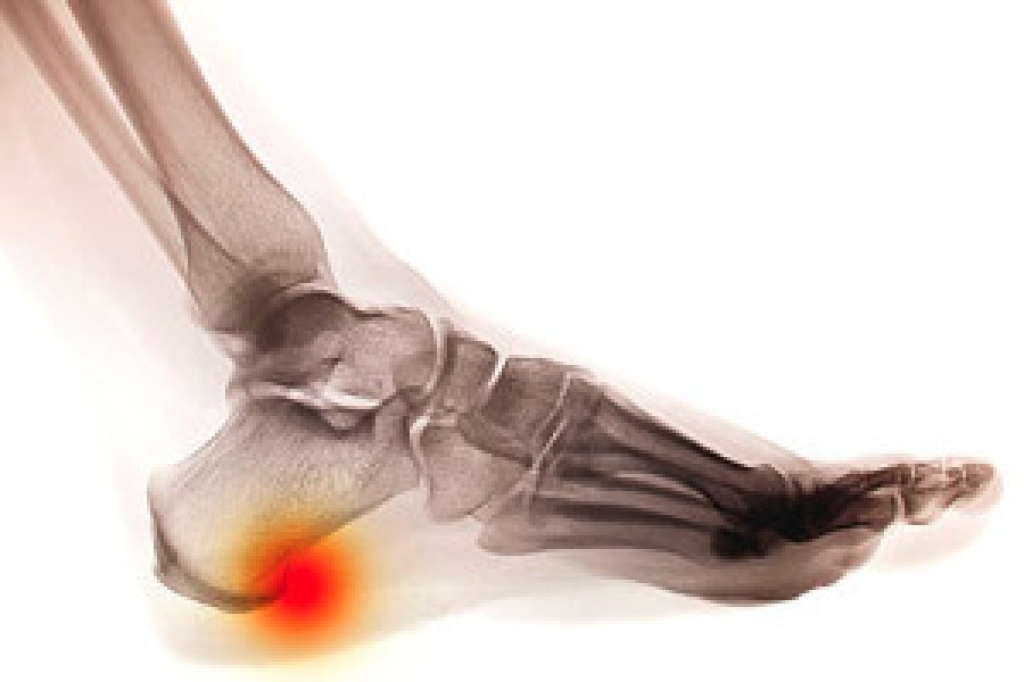

To figure out the cause of foot pain, podiatrists utilize several different methods. This can range from simple visual inspections and sensation tests to X-rays and MRI scans. Prior medical history, family medical history, and any recent physical traumatic events will all be taken into consideration for a proper diagnosis.